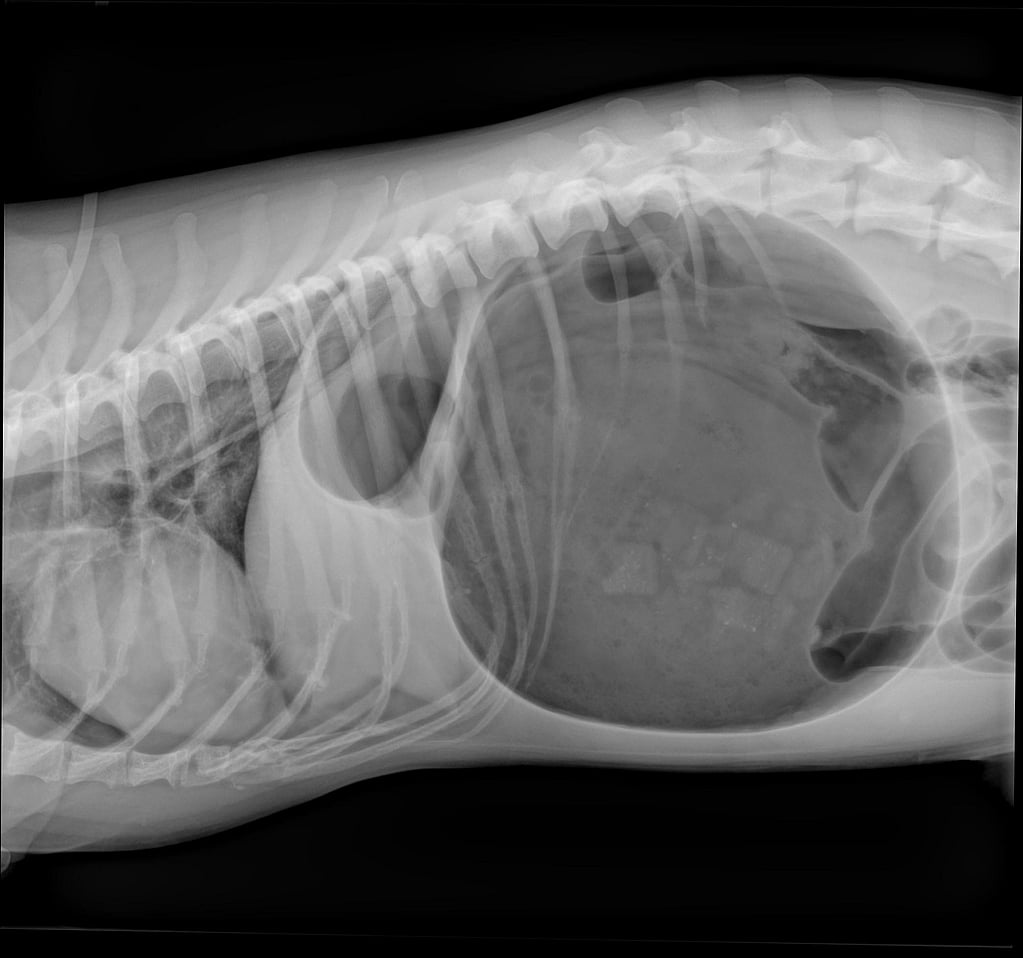

Hierna werden RX-foto’s genomen om het vermoeden van een maagkanteling te bevestigen. Bijgevoegde RX-foto’s in rechts laterale en ventrodorsale positie tonen een gedilateerde en gedraaide maag met de typische ‘double bubble’.